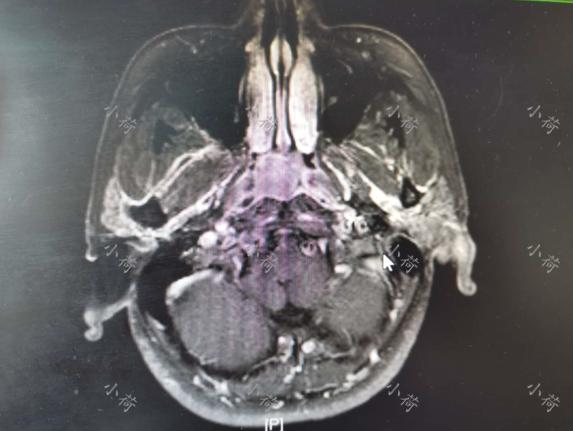

6年前,我接诊了这位53岁的男性患者,他有半年多的时间鼻涕回吸带血,量不大,略频繁,无其他不适症状,无贫血,因为这次鼻出血,在我建议下,过来检查,在门诊做了鼻咽部MRI(图1),并做了纤维鼻咽镜检查,取了活检,确诊为鼻咽癌。患者还有高血压病史,目前血压控制稳定。入院时,病理结果已经出来,诊断为鼻咽癌,高血压Ⅱ级。

图1 鼻咽部MRI显示局部病变